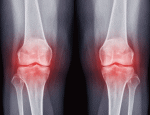

■ 変形性膝関節症 osteoarthritis

変形性膝関節症とは

❑ 膝関節軟骨の弾力性の低下、摩耗、変形によって生

じる病気です。

■ 変形性膝関節症の診断

◇ レントゲン検査

アライメント、関節裂隙狭小化、Kellgren-Lawrence

(KL)分類等で重傷度の評価。